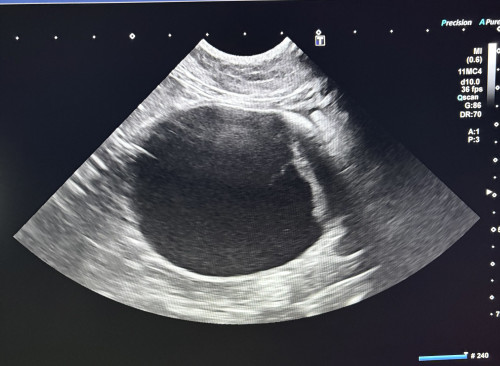

こちらは来院された猫ちゃんのエコー検査した時の膀胱です

おしっこが出ないで溜まってしまって膀胱がパンパンになっています💦

この状態になってしまうと緊急処置が必要です。